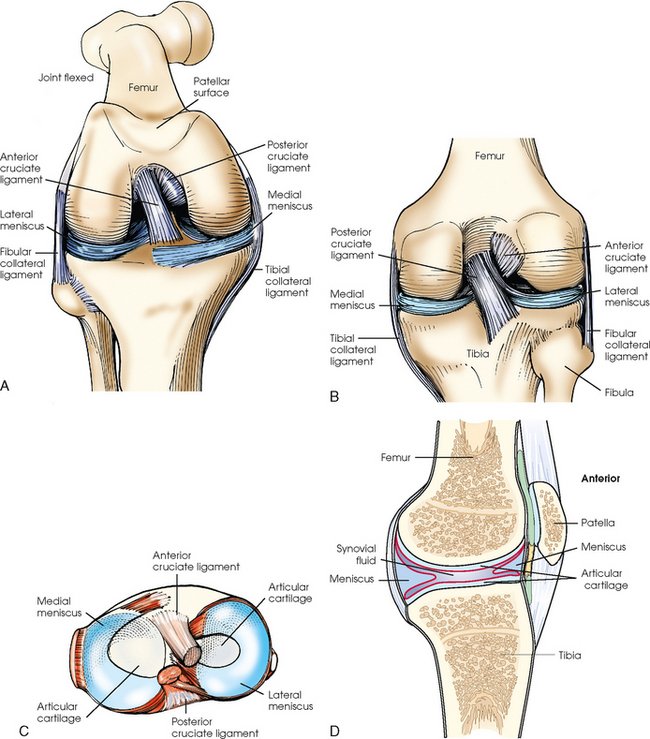

The knee joint is one of the most complex joints in the human body. The femur, tibia, fibula, and patella are held together by a complex group of ligaments. These ligaments work together to provide stability for the knee joint. Although radiographers do not produce images of these ligaments, they need to have a basic understanding of their positions and interrelationship. Many patients with knee injuries do not have fractures, but they may have torn one or more of these ligaments, which can cause great pain and may alter the position of the bones. Fig. 6-9 shows the following important ligaments of the knee:

Fig. 6-9 Knee joint. A, Anterior aspect with femur flexed. B, Posterior aspect. C, Superior surface of tibia. D, Sagittal section.

The knee joint contains two fibrocartilage disks called the lateral meniscus and medial meniscus (Fig. 6-10; see Fig. 6-9). The circular menisci lie on the tibial plateaus. They are thick at the outer margin of the joint and taper off toward the center of the tibial plateau. The center of the tibial plateau contains cartilage that articulates directly with the condyles of the knee. The menisci provide stability for the knee and act as a shock absorber. The menisci are commonly torn during injury. Either a knee arthrogram or a magnetic resonance imaging (MRI) scan must be performed to visualize a meniscus tear.